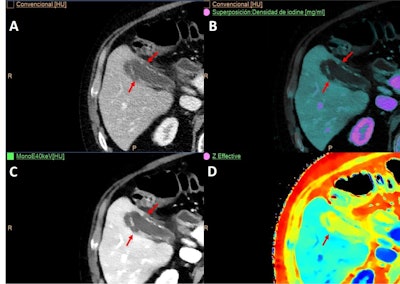

An 85-year-old man with previous rectal tumor and abdominoperineal excision of the rectum had a follow-up CT exam. (A) Conventional image shows an indeterminate soft tissue lesion at the anastomotic site that is barely visible. Virtual low keV monoenergetic image (B) and Z-effective (C) improve detection of this enhancing mass compared to conventional image. (D) Spectral map such as iodine no water also makes it possible to quantify the iodine uptake, which was 1.3 mg per mL in this case. All these findings were in keeping with local tumoral recurrence in the anastomotic site.